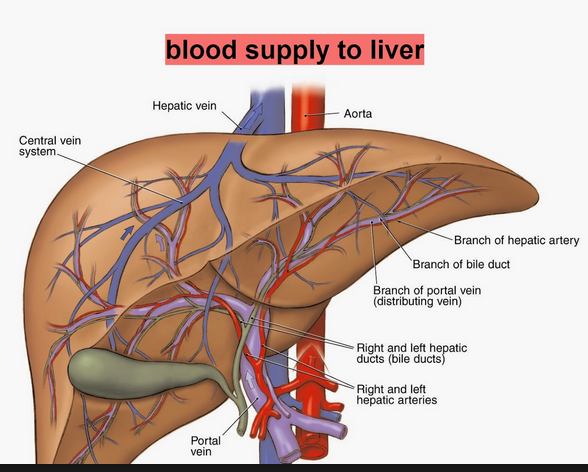

36 blood software